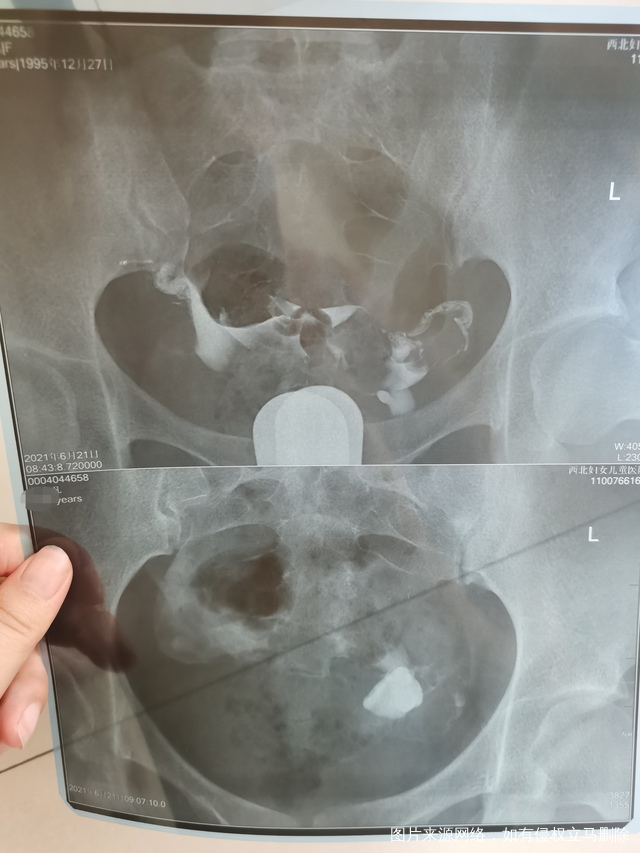

做完输卵管造影第六天了小腹还是感觉沉甸甸的如

可以热敷腹部,如果有发热,腹痛加剧,白带量多,有异味,随时就医